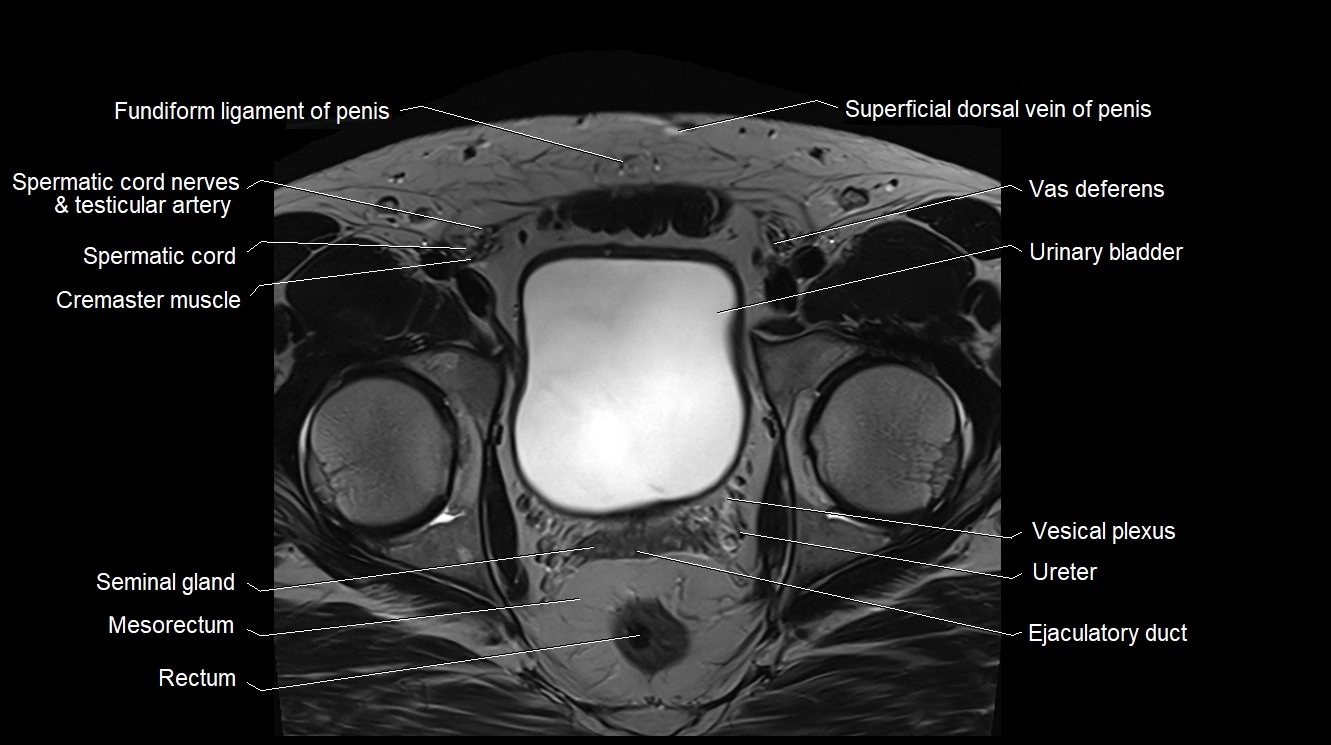

MRI image